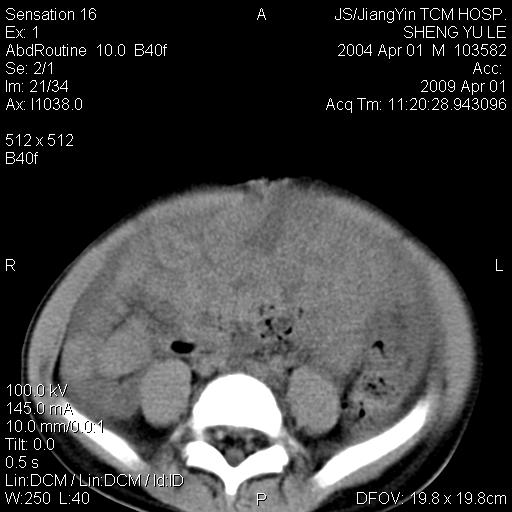

m,5岁。尿痛尿频数天。既往无病史。ct平扫腹盆腔积液。膀胱壁明显增厚。另可见心包增厚。wbc5万,骨髓穿等结果。请指教。

膀胱影像表现结合临床应该是急性膀胱炎症,但为什么有腹水呢?双肾输尿管无扩张,泌尿系压力应该不大不至于引起尿外渗,应该是腹膜感染引起的,但楼主没有提及相关症状,腹膜及膀胱结核?患者白细胞5万(结核不至于这么高啊),脾脏增大,是不是有白血病?进一步检查。。

腹水,膀胱壁增厚,wbc5万,结合临床,支持感染性疾病---感染性腹膜炎、腹水,急性膀胱炎,败血症。期待结果。